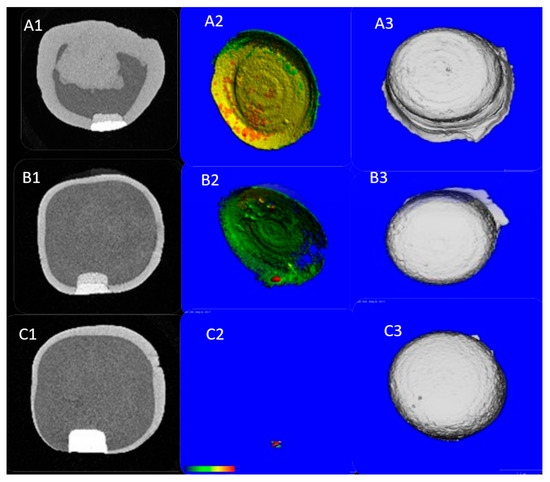

3.1. MCT Findings

3.2. OCT Findings